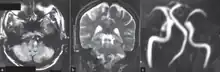

Since lateral medullary syndrome is often caused by a stroke, diagnosis is time dependent. Diagnosis is usually done by assessing vestibular-related symptoms in order to determine where in the medulla that the infarction has occurred. Head Impulsive Nystagmus Test of Skew (HINTS) examination of oculomotor function is often performed, along with computed tomography (CT) or magnetic resonance imaging (MRI) to assist in stroke detection. Standard stroke assessment must be done to rule out a concussion or other head trauma.[1]